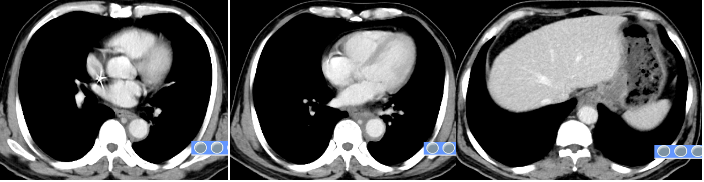

替雷利珠单抗+化疗联合治疗前影像

替雷利珠单抗+化疗联合治疗2周期后影像

2周期治疗后患者吞咽困难症状缓解。2、4周期复查CT:胸下段及腹段食管癌并纵隔淋巴结转移累及胃贲门较前明显缩小,胃小弯侧及腹膜后多发淋巴结转移累及胃小弯壁较前明显退缩。后续计划提交本院食管癌MDT讨论拟定下一步行手术或局部放疗。